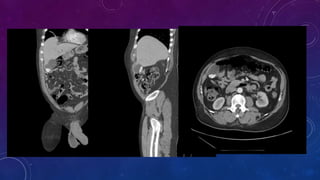

FAILED BILATERAL RENAL TRANSPLANTS

CALCIFICATION

RIGHT RENAL ARTERY ANEURYSM

RUPTURED MYCOTIC ANEURYSM FROM BRUCELLOSIS